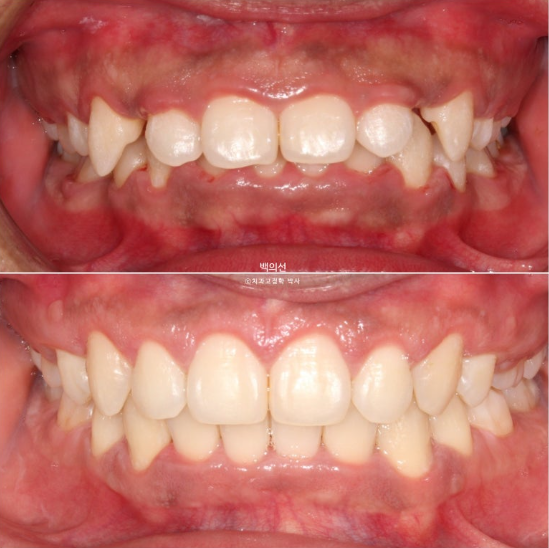

이제 전후 비교 보겠습니다.

중심선은 잘 맞으며 과개교합은 좋아졌습니다.

안모에서는 확실한 거미스마일 개선이 눈에 띕니다.

앞니가 상당히 뒤로 들어갔음에도 치료 전과 후 입매 변화가 크지는 않습니다.

인중 부위의 볼롬함 감소와 아랫입술의 후퇴 정도만 눈에 띕니다.

위 앞니 기준 뒤로 4-5mm 들어갔고 위로는 2-3mm 함입되었습니다.